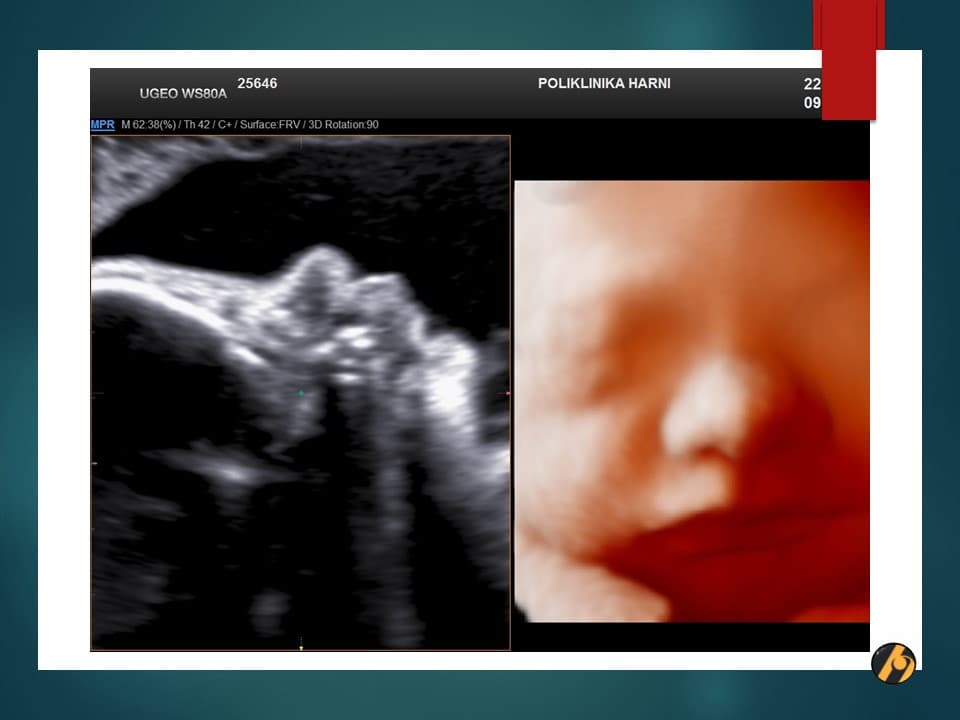

S 37. tjednom trudnoće Vaša beba postaje klinički zrela i potpuno spremna za porod. S ovim tjednom se također završava razdoblje mogućeg preranog poroda.

U sljedećim danima beba će i dalje dobivati na težini, pri čemu se ovaj dobitak osobito odnosi na odlaganje masnog tkiva. U ovo vrijeme beba odlaže u prosjeku 14 g masti/dan. Esencijalne masne kiseline ulaze i u sastav mijelina, specijaliziranog omotača moždanih i kičmenih živaca čime započinje i konačni proces dozrijevanja živčanog sustava. Ovaj proces mijelinizacije nastaviti će se i nakon bebinog rođenja.

Vaša beba dugačka je oko 47 cm, i teška 2,750 – 2,950 g.